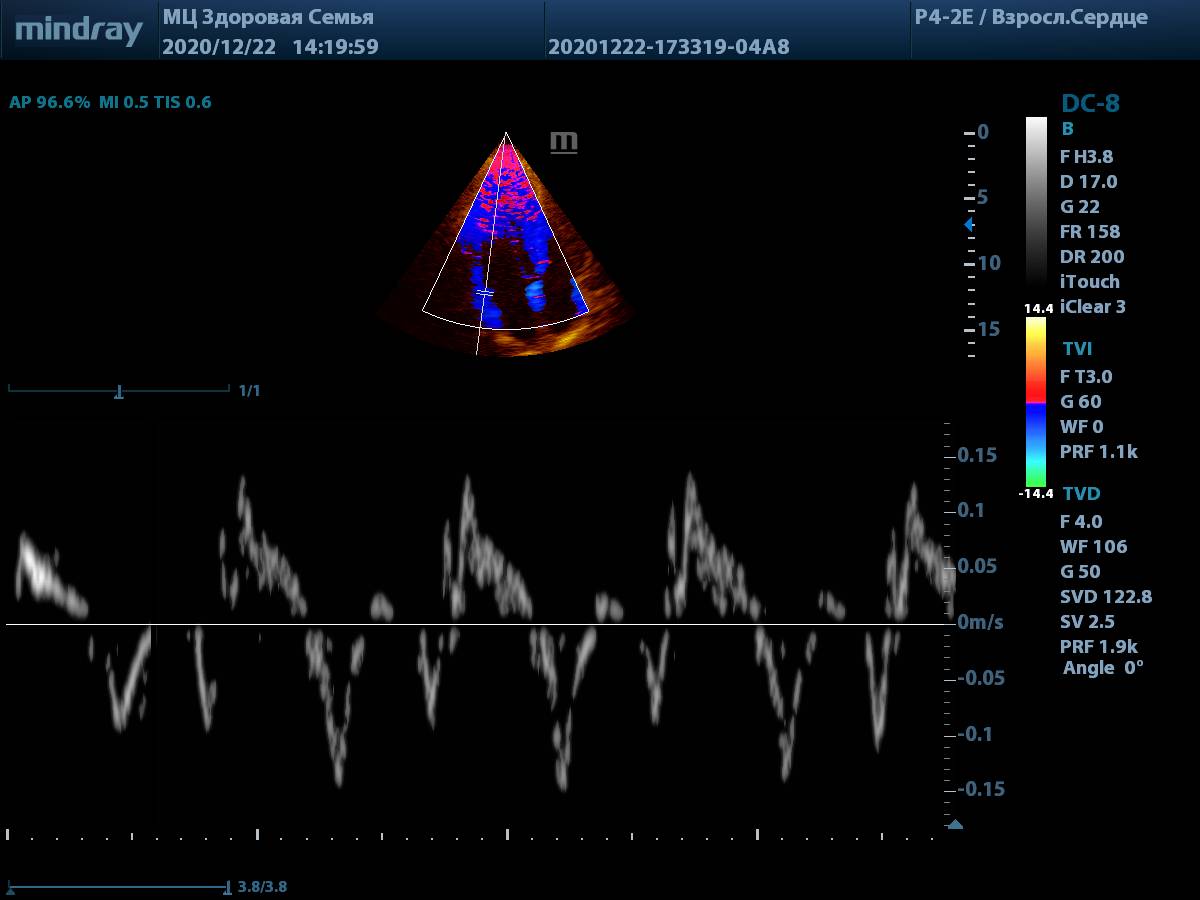

3. Тканевая допплерография (TDI). Всё просто и удобно, достаточно нажать одну кнопку. Цветовая карта по умолчанию яркая, не нужно настраивать её усиление для выбора точки установки контрольного объема.

Тканевая допплерография (TDI)